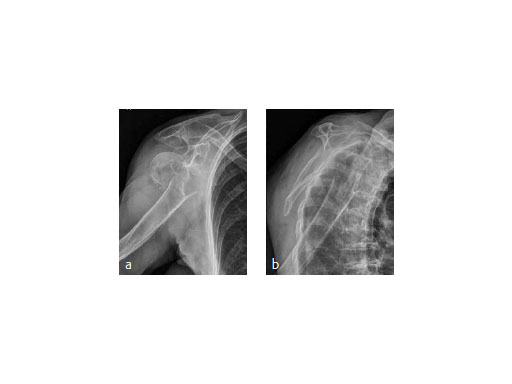

A 91-year-old female patient with osteoporosis had a dislocated 3-part proximalhumeral fracture in her right dominant arm (Fig 8).

The fracture was treated with PHILOS augmentation and healed in anatomical position (Fig 9).